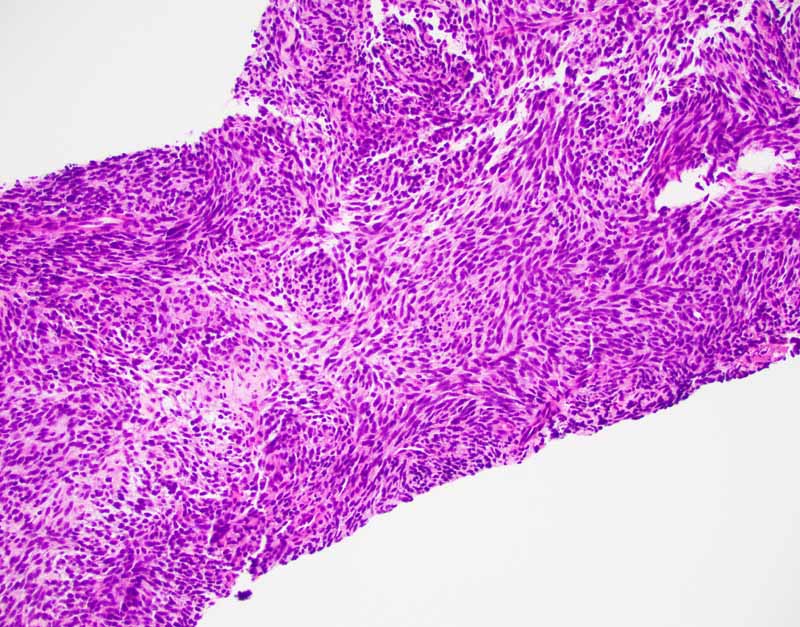

Histology of the Case: The lesion is an encapsulated neoplasm a glandular component and a myxoid component (Panel I and J). The two comonents are well demarcated without transition from one into another. Although the myxoid component (Panel K and L) is not present in the cell block of the FNA, the myxoid substance of the FNA comes from this myxoid component. The glandular component (Panel M, N, O, P) is composed of well formed glands with PAS positive mucoid content in the lumen (Panel Q). In between the well formed glands are spindle cells with nuclear features identical to that of the glands (S in Panel N). This component is present in the cell block of the FNA and is the major clue for the diagnosis.

The classic biphasic type is readily recognizable by the presence of epithelial component in a background of spindle cells similar to fibroblasts. Well-defined sharp transition rather than gradual transition is typical between the epithelial and spindle cell component. The glandular growth pattern can vary from obvious to vague and, in the later case, clefts resulted from shrinkage due to processing must not be mistaken as genuine glandular lumens. The glandular epithelial cells are usually cuboidal to columnar. Secretions within the lumen can be seen and squamous metaplasia may be present. The spindle cell component is typically composed of monotonous well-oriented plump spindle cells with indistinct cytoplasm and oval to elongated hyperchromatic nuclei. Fibrotic areas with hyalinization and myxoid changes can be found. In about 20% of cases, calcifications with or without ossification is present and act as a good diagnostic clue. Substantial number of mast cell is another diagnostic clue.

Monophasic fibrous synovial sarcoma is typically composed of monotonous solid sheets of small spindle cells with indistinct cytoplasmic membrane and small hyperchromatic nuclei without nucleoli. Vague palisading arrangement can be present. Usually, there is no intervening collagen fibers. Some foci of epithelioid morphology can be seen. Secondary changes such as calcifications and myxoid changes as seen in the spindle cell component of the biphasic type can also be found. Staghorn shaped blood vessels similar to those in hemangiopericytoma can be part of the histopathologic picture.